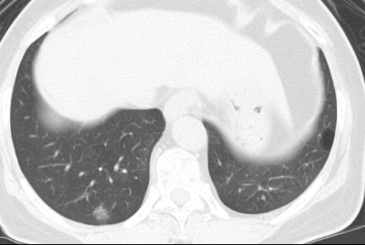

原発性肺癌のCT所見

- 典型的な原発性肺癌

- 早期の肺腺癌

転移性肺癌のCT所見